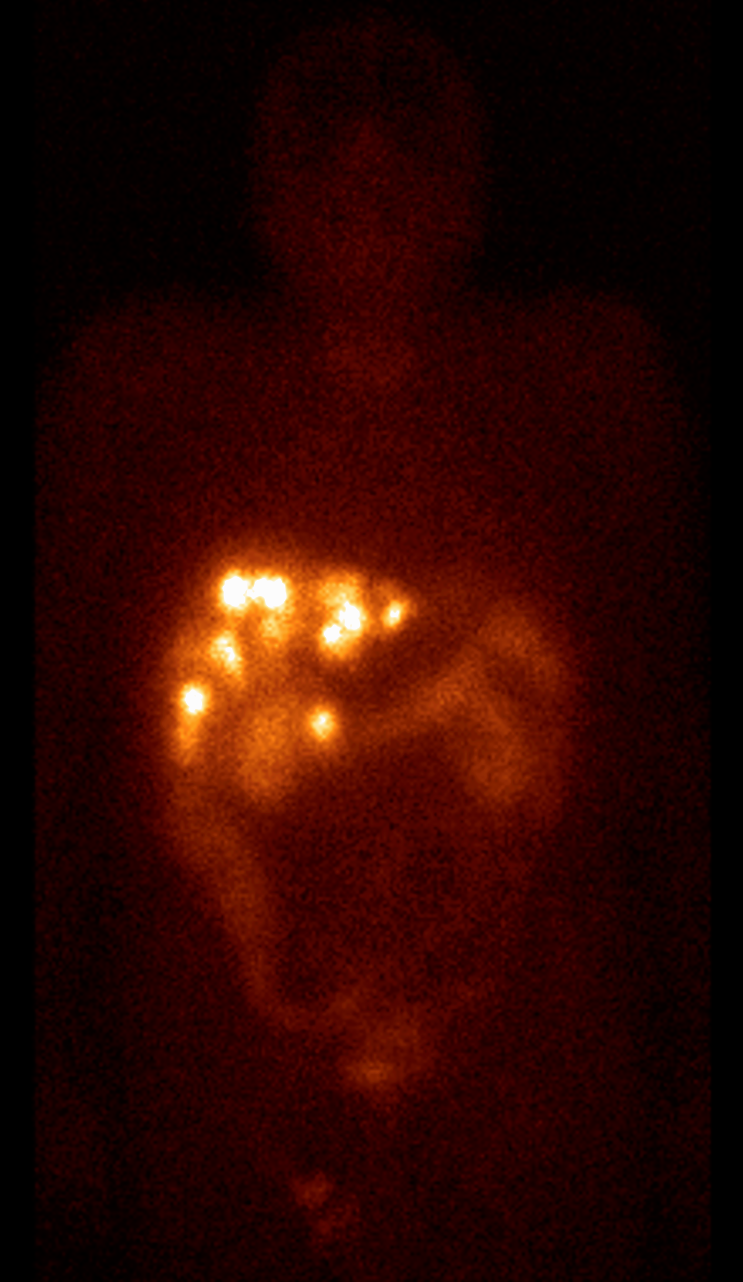

In cases of primary bone tumors, three phase scintigraphy can help to determine the dignity of equivocal bone lesions. Benign lesions do not show typically increased activity in the early phases, and even if there is a detectable late phase activity, it is moderate (except for osteoid osteoma, osteoblastoma, fibrotic dysplasia and aggressively growing bone cysts, or lesions that are associated with pathologic fractures.) Malignant tumors (osteosarcoma, Ewing sarcoma) as opposed to benign tumors, have an increased blood supply and a more intense osteoblast activity. (Figure 6.)

6. Osteosarcoma in the right femur. Three phase bone scintigraphy, planar anterior images. Perfusion phase acquisitions (a), summation (b), early blood pool phase (c), late phase (d), whole body scan (e).

Scintigraphy is also helpful in determining any skip lesions and bone metastases that are normally associated with malignant tumors. It is also useful in monitoring preoperative chemotherapy, and tumor recurrence. In osteosarcoma, because of the tumor’s osteoid production, it is also possible to detect soft-tissue metastases (e.g.: lung metastases). Tumor-specific nuclear medicine examinations, such as FDG-PET are useful for the staging and re-staging of the tumors and in monitoring chemotherapy. Uncertain processes can be differentiated by FDG-PET, since low grade sarcomas have no or minimal glucose metabolism, while high grade sarcomas have high glucose metabolism. Concerning benign tumors, scintigraphy is basically 100% sensitive for osteoid osteoma. Its nidus shows an intensive, dot-like activity increase in all three phases of the examination. Since the activity accumulation in osteoid osteoma is so intense, isotopic methods (intraoperative scintigraphy or gamma probe) can be used as a guiding tool during surgery.